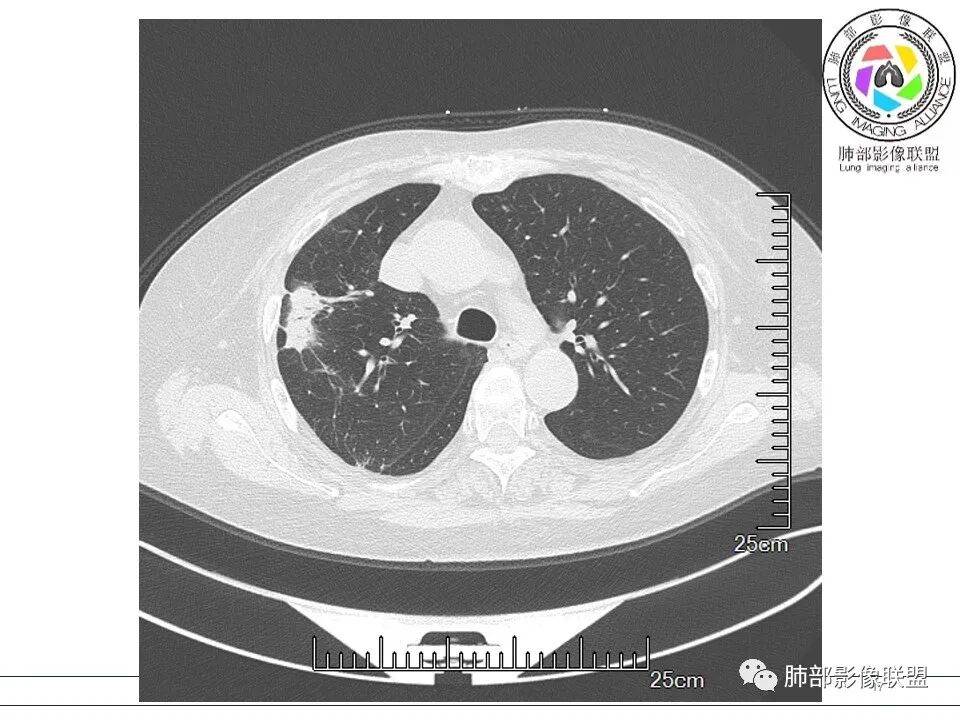

放射小白: 晨读病例:女性,70岁,风湿性多肌痛病史,右肺见不规则结节,边缘及周围见纤维索条影,考虑OP,药物性肺损伤。

小兜: 晨读,女,70岁,风湿性多肌痛病史一年,半月前体检发现肺部阴影,无症状,口服药物治疗。现片示:右肺胸膜下条形实变影,局部层面似见多结节融合,周边伴条索影。下方近叶间胸膜处斑片状实变影伴条索影,宽基底与胸膜相连。综合考虑为炎性病变,隐球菌或OP可能

宇宙: 右肺上叶胸膜下结节,多结节融合,长轴平行胸膜,边缘模糊,周围长索条,胸膜牵拉,近端支气管充气扩张,考虑隐球菌,鉴别OP

玫: 晨读:右肺上叶胸膜下软组织密度影,边缘模糊,周围见条索影及少许磨玻璃影,轻度胸膜牵拉,考虑炎性病变。

衡妈: 老年女性,右肺上叶沿胸膜下不规则实性病灶,长轴平行于胸膜,有结节融合感,边缘部分彭隆部分平直,周围可见数条纤维灶影,病灶内可见充气支气管征未达远端,首诊考虑慢性炎性肉芽肿,隐球菌?机化性肺炎?建议增强扫描及ct下穿刺活检。

晨读:女,70,未诉症状。风湿性多肌痛病史,口服强的松等药物治疗。胸部CT:右肺上叶多发不规则斑片影,沿支气管分布,部分病灶侧向融合、平行于胸膜,边缘平直内收为主、部分彭隆,周围模糊晕、可见数条纤维灶影,胸膜牵拉,病灶内可见充气支气管征、管腔不畅,考虑慢性炎症,PC?OP?鉴别腺Ca、SCLC等。